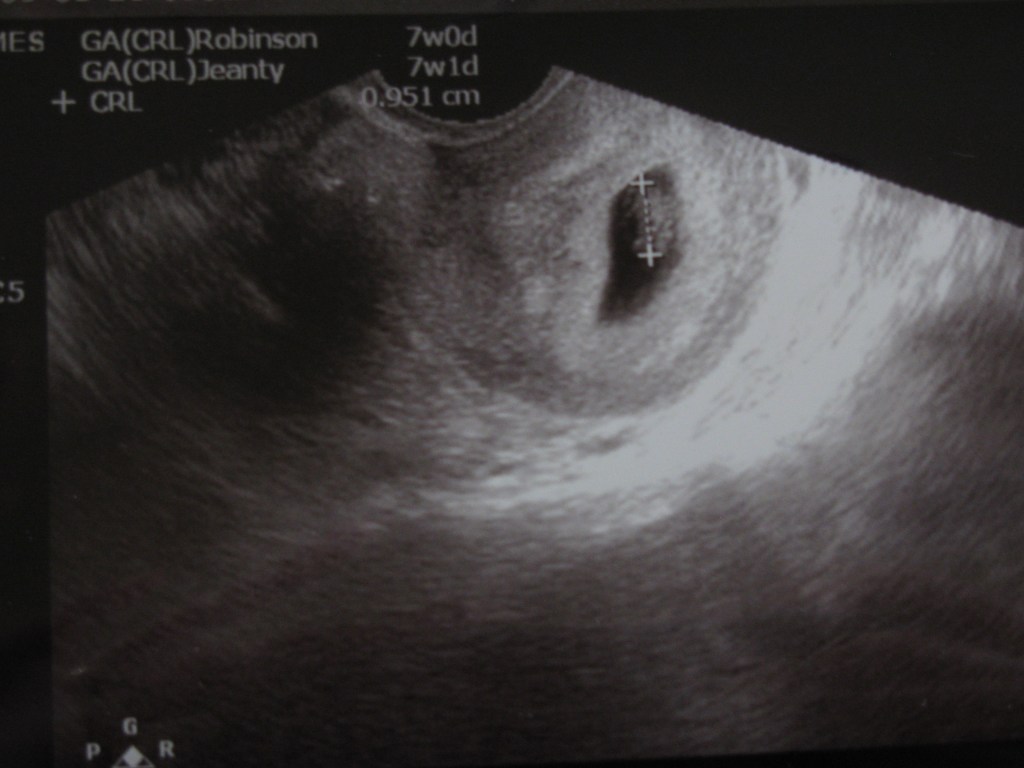

And since we’re in a picture mood, here’s also one from a few weeks back, when we got confirmation that little peanut was there: